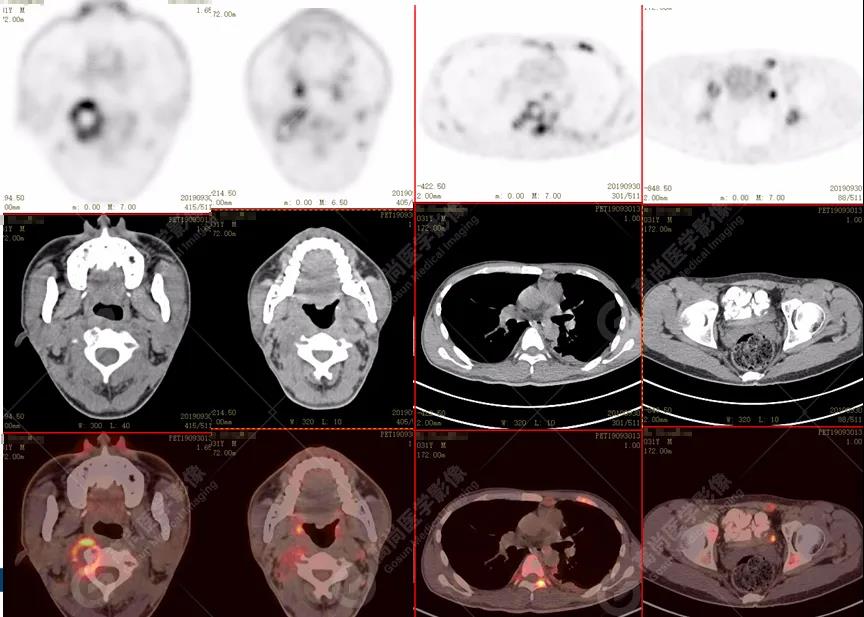

診斷思路:

1.全身未找到原發(fā)腫瘤病灶;

2.全身多系統(tǒng)、多形態(tài)、多發(fā)病灶(肺部、胸膜、淋巴結(jié)、骨),18F-FDG攝取不均性增高;

特征:肺部病灶簇狀分布,上葉尖段及下葉背段為著;腫大淋巴結(jié)分布不對稱,無融合、中央有壞死改變,與淋巴瘤、轉(zhuǎn)移瘤等有一定的鑒別診斷意義;

診斷意見:綜合考慮感染性病變(結(jié)核),建議相關(guān)實(shí)驗(yàn)室檢查。

在PET/CT的提示下,患者遂在醫(yī)院行痰結(jié)核菌檢查,結(jié)果結(jié)核桿菌陽性,故確診結(jié)核,排除轉(zhuǎn)移瘤及其他類型感染。